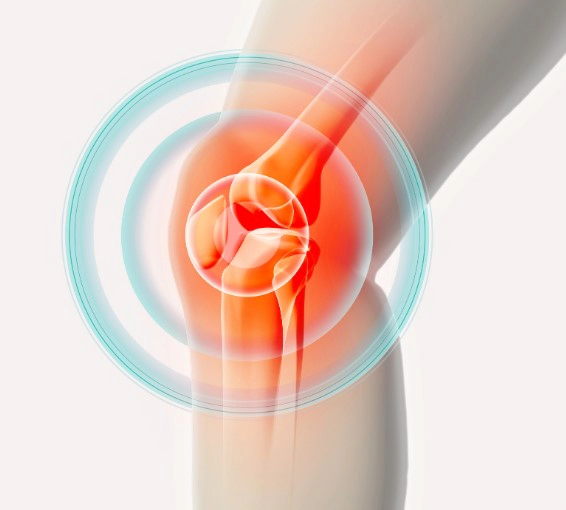

1. 무릎 관절염 증상

무릎 관절염은 무릎 관절의 염증과 관련된 질환으로, 연골 손상, 관절 주위의 연조직의 염증, 뼈의 변형 등 다양한 원인이 있을 수 있습니다.

1.1. 통증

무릎 관절염의 가장 일반적인 증상은 통증입니다. 통증은 일상 생활에서 움직임이나 활동을 제한할 정도로 심해질 수 있으며, 휴식을 취하면 완화될 수 있습니다. 통증은 무릎 관절 내부의 염증, 연골 손상, 뼈의 변형 등으로 인해 발생합니다.

1.2. 관절의 팽만

무릎 관절 주위에 있는 연조직의 염증으로 인해 관절이 붓고 팽만할 수 있습니다. 팽만은 보통 통증과 함께 나타나며, 휴식을 취하면 완화될 수 있습니다.

1.3. 운동 범위 감소

무릎 관절염이 진행되면서 연골이 닳거나 뼈가 변형되면 관절의 움직임이 제한될 수 있습니다. 이로 인해 일상 생활에서의 움직임이 불편해지고, 무릎을 완전히 굽히거나 펴기 어려워질 수 있습니다.

1.4. 딱딱거리는 소리 발생

무릎 관절을 움직일 때 뼈가 서로 부딪히거나 마찰로 인해 딱딱한 소리가 날 수 있습니다. 이 소리는 무릎 관절의 연골이 닳거나 뼈가 변형된 결과일 수 있습니다.

1.5. 관절의 변형

무릎 관절염이 심해지면 뼈의 변형이 발생할 수 있습니다. 이로 인해 무릎 관절이 비정상적인 모양을 갖게 되며, 심한 경우에는 무릎을 완전히 굽히거나 펴지 못하게 됩니다.